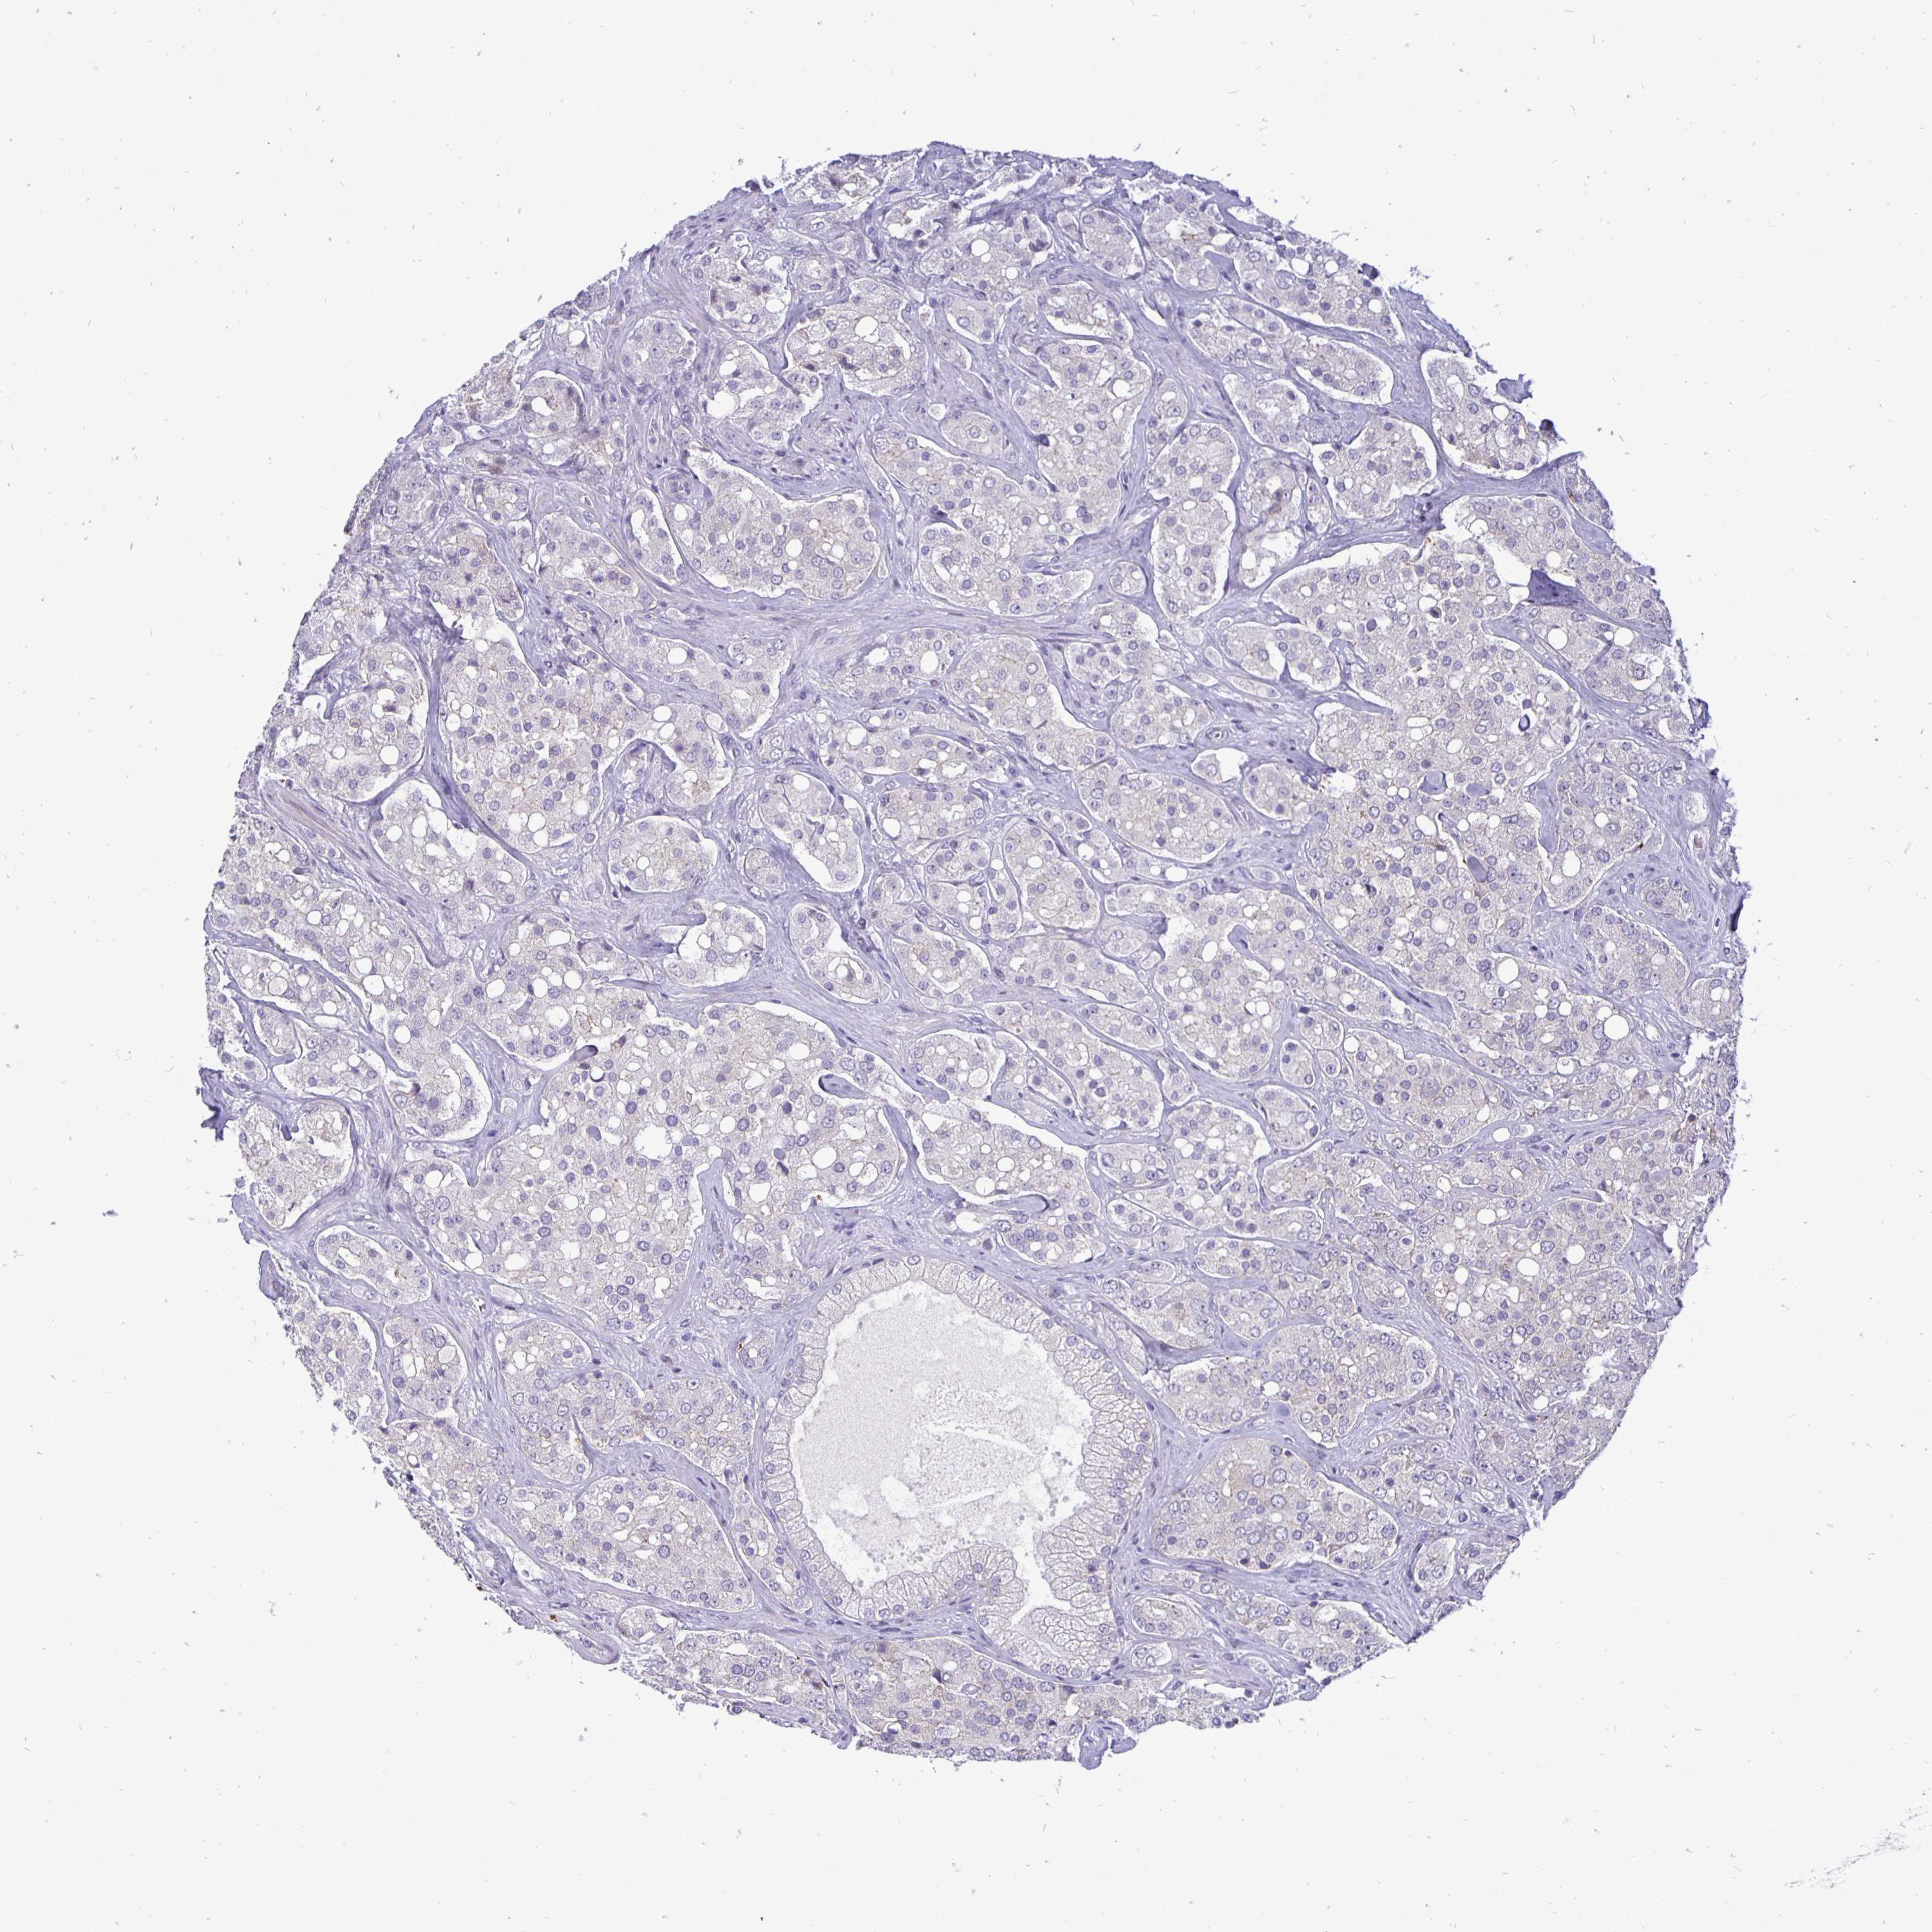

PROSTATE CANCER - Protein expressioni

A mouse-over function shows sample information and annotation data. Click on an image to view it in a full screen mode. Samples can be filtered based on level of antibody staining by selecting one or several of the following categories: high, medium, low and not detected. The assay and annotation is described here.

Antibody stainingi

Antibody staining in the annotated cell types in the current human tissue is reported as not detected, low, medium, or high, based on conventional immunohistochemistry profiling in selected tissues. This score is based on the combination of the staining intensity and fraction of stained cells.

Each image is clickable and will lead to virtual microscopy that enables deeper exploration of all samples and also displays staining intensity scores, fraction scores and subcellular localization as well as patient and tissue information for each sample.

Antibody HPA001383

Antibody CAB000043

Antibody CAB020416

Antibody CAB062555

Adenocarcinoma, Medium grade

Adenocarcinoma, Low grade

Adenocarcinoma, High grade

Adenocarcinoma, NOS